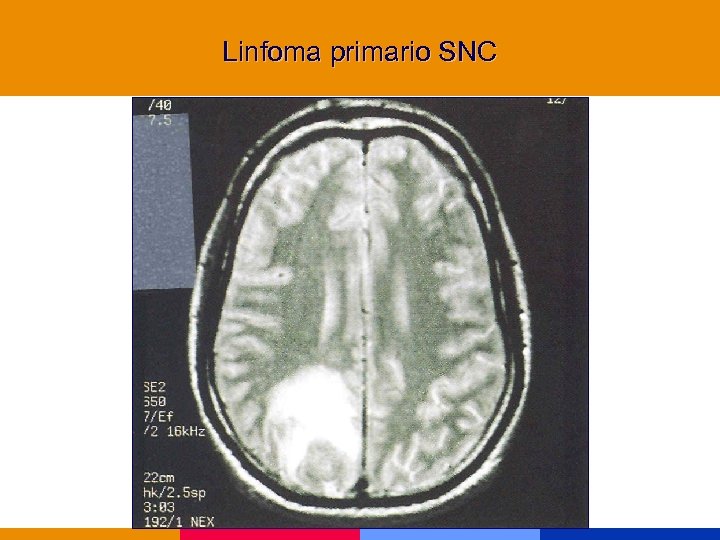

Linfoma § Inmunocompromiso severo. § Confusión, trastornos mnésicos, foco, convulsiones, pares craneanos. § Lesiones hipodensas que refuerzan contraste. Gralmente. únicas (50% múltiples en RMN). § Asociado a EBV. Detección en biopsia o LCR. § Trat. : radioterapia

Linfoma § Inmunocompromiso severo. § Confusión, trastornos mnésicos, foco, convulsiones, pares craneanos. § Lesiones hipodensas que refuerzan contraste. Gralmente. únicas (50% múltiples en RMN). § Asociado a EBV. Detección en biopsia o LCR. § Trat. : radioterapia

Linfoma primario SNC

Linfoma primario SNC

Linfoma SNC

Linfoma SNC

Linfoma SNC

Linfoma SNC

Neoplasias marcadoras § Cáncer de cuello uterino, invasivo § Sarcoma de Kaposi § Linofoma no Hodking, primario de SNC Incremento de otras neoplasias: pulmón, seminoma, melanoma, otras

Neoplasias marcadoras § Cáncer de cuello uterino, invasivo § Sarcoma de Kaposi § Linofoma no Hodking, primario de SNC Incremento de otras neoplasias: pulmón, seminoma, melanoma, otras

Linfoma primario SNC

Linfoma primario SNC